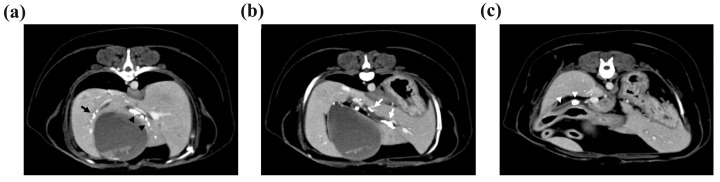

Computed tomography (CT) was performed to determine the size and location of the gallstones and whether there was obstruction or dilatation of the biliary system for surgical planning. The CT scan revealed cholelithiasis in the GB, the left, quadrate, and right liver lobes, and the CBD (Figure 2). Multiple intrahepatic gallstones were observed, and the hepatic duct in the left medial liver lobe was dilated with a diameter of 4 mm. The CBD was also dilated to 7 mm, and two gallstones were also identified.